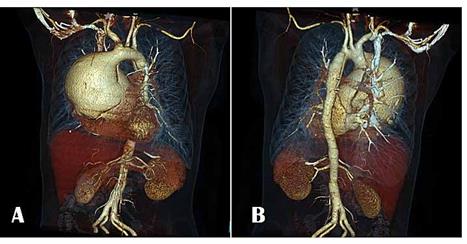

Aortografía (Imagen 3 y 4).

IMAGEN 2. Reconstrucción tridimensional de aortografia por TC: Observe

flechas Aneurisma sacular

disecante de aorta

ascendente con extensión al cayado y parte de aorta descendente (Tipo A de Stanford). Imagen A reconstrucción imagen lateral, Imagen B reconstrucción imagen frontal.

Fuente. Base de datos de la investigación.

Elaborado por. Autores.